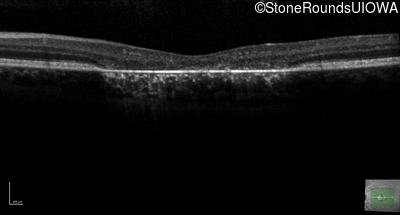

This 22 year old man had macular abnormalities noted incidentally at a routine eye exam at age 19. Since then, he has experienced a gradual loss of acuity particularly in the left eye.